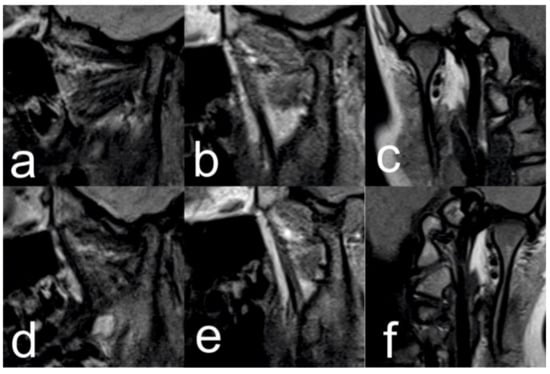

2.1. Initial Diagnosis and Initial Surgical Management

2.3.1. First Treatment Phase—2016—TMJ Splint Therapy